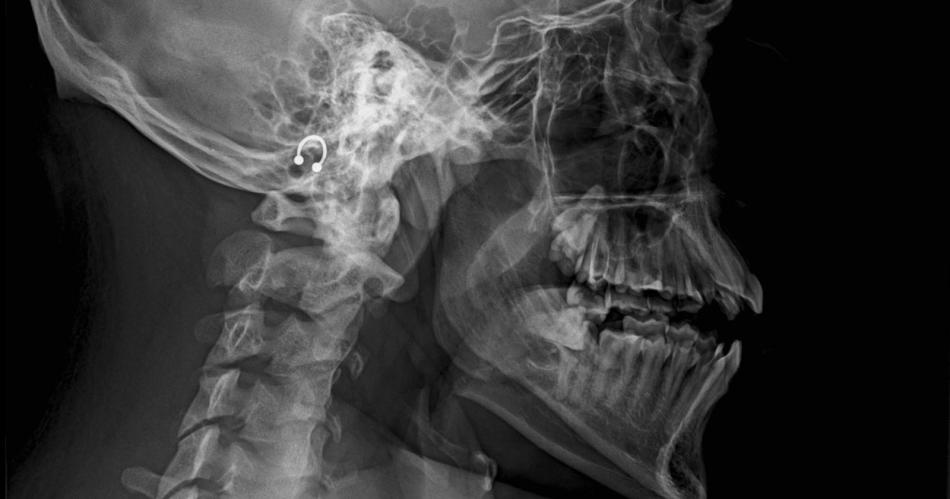

"Doble fractura de mandíbula con desplazamiento de piezas dentarias (comprometidas)". El diagnóstico corresponde a un joven que protagonizó un entredicho en una cancha de fútbol 5, ocasión en la que habría sido agredido por dos rivales, en especial uno de ellos que lo atacó de atrás.

"Me contó que después, siguieron golpeándolo. Intervinieron amigos de su equipo y pudieron contenerlos. Sangrando, llevaron a mi hijo al Hospital Independencia. Lo asistieron, contuvieron la sangre, pero tiene doble fractura de mandíbula y debe ser intervenido quirúrgicamente", continuó.